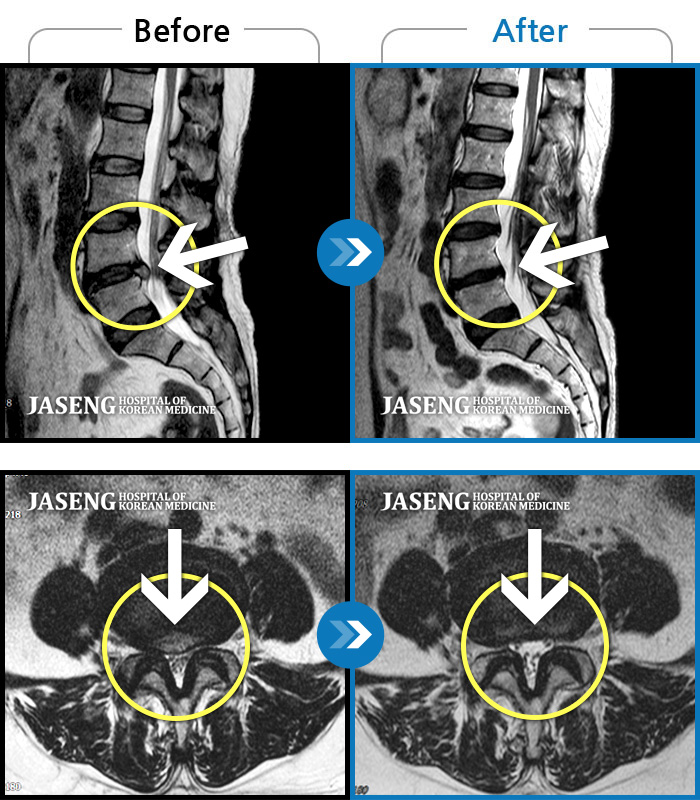

MRI 치료사례

내원 당시 추간판 탈출 및 척추관 협착증으로 잠자기 어려울 정도의 요통 및 오른쪽 골반~종아리 저림으로 일상생활이 어려우셨던 분입니다.